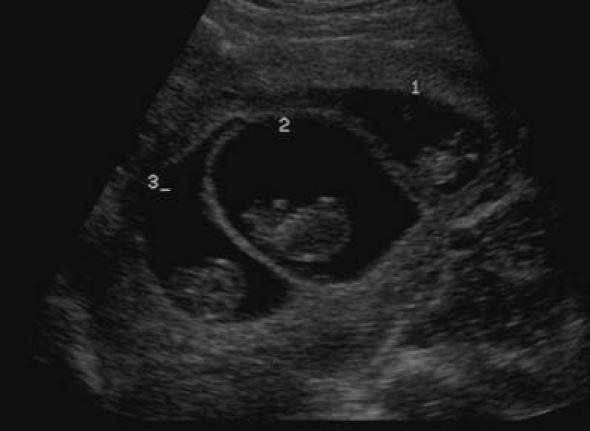

Σήμερα τα ξημερώματα, η 33χρονη γυναίκα, έφερε στον κόσμο τα τρία υγιέστατα αγοράκια, βάρους 1200 ως 1400 γραμμαρίων. Τον τελευταίο χρονικό διάστημα η έγκυος  νοσηλευόταν στο Πανεπιστημιακό Νοσοκομείο Ηρακλείου στη Μαιευτική- Γυναικολογική Κλινική. Τα έμβρυα βρίσκονταν σε τρεις σάκους αλλά τρέφονταν από τον ίδιο πλακούντα. Μια περίπτωση σπάνια, για την οποία υπήρχε πάντα ο κίνδυνος της επιπλοκής, μιας και σε τέτοιες εγκυμοσύνες είναι πιθανή η «υποκλοπή αίματος» του ενός εμβρύου από τα άλλα.

Τα μωράκια γεννήθηκαν πρόωρα μεν σε καλή κατάσταση δε. Όπως εξηγεί ο κ. Σηφάκης, μιλωντας αποκλειστικά στο CretePlus.gr: «η περίπτωση αυτή είναι πολύ σπάνια, καθώς τα μωρά τρέφονταν και αναπτύσσονταν από τον ίδιο πλακούντα. Πρόκειται για μονοζυγωτική, μονοχοριακή, τριαμνιακή κύηση.